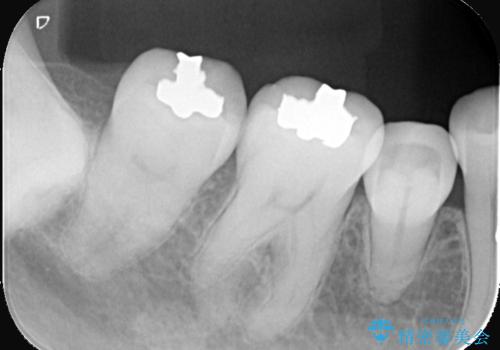

- 主訴:口を開けると所々入っている銀の詰め物が目立つので白い物にやり替えたい。

下顎大臼歯部に入っている保険適用のメタルインレーを、適合性と審美性の良いセラミックインレーでのやり替えとなりました。

メタルインレーを除去した際、古い裏層材やカリエスは除去し新たにCR裏層しています。